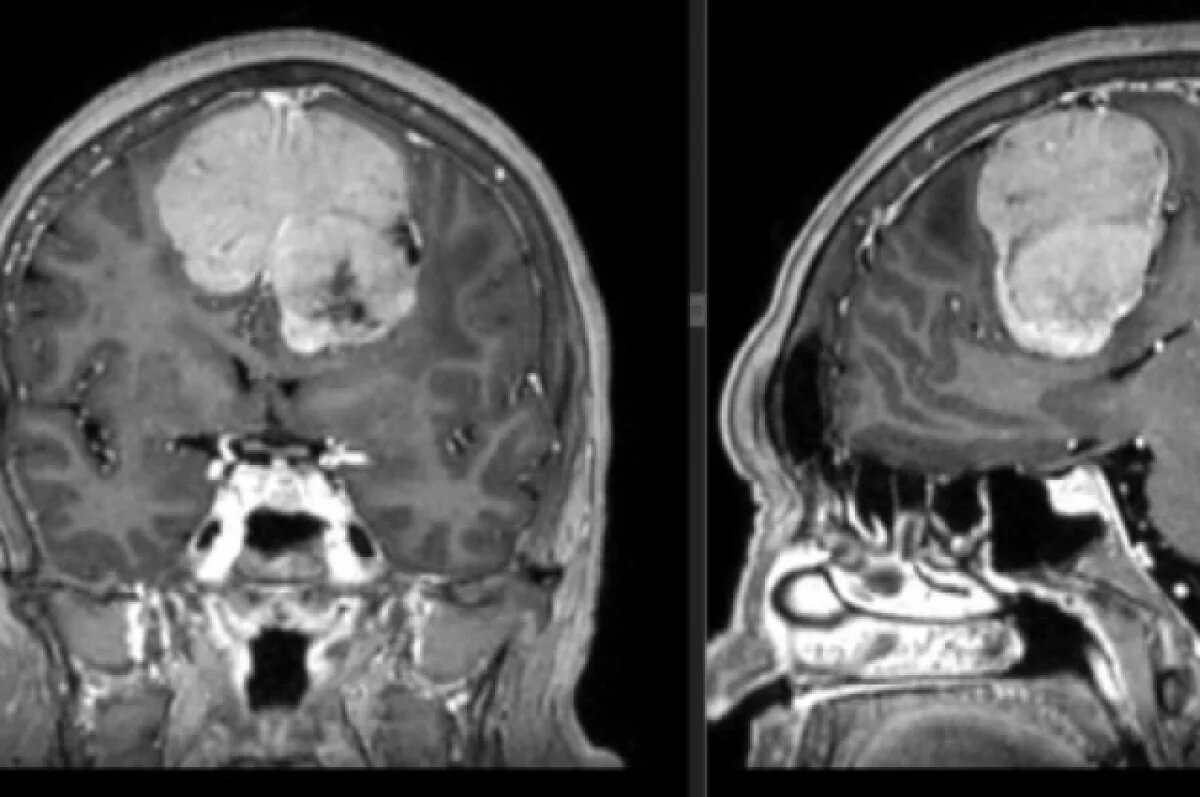

Опухоль, объёмом 189 кубических сантиметров, удалили из головы жительницы региона, сообщает Минздрав Удмуртии.

В ижевскую городскую клиническую больницу № 7 обратилась 60-летняя женщина с жалобами на головные боли и потерю памяти. Во время обследования у неё обнаружили гигантскую опухоль, которая занимала почти 14% объёма полости черепа.

«Тревогу забили её коллеги, когда женщина стала ошибаться в документах и перестала справляться со своими рабочими обязанностями, изменился характер, она перестала ухаживать за собой. Родственники отправили её на обследование, где была выявлена опухоль мозга – менингиома больших размеров. Было принято решение о проведении операции, которая длилась более 5 часов», – сказал врач-нейрохирург Ольга Мурашова.

Новообразование удаляли нейрохирурги ГКБ № 7 Владимир Пашкин и Ольга Мурашова. Врачам удалось полностью удалить опухоль, сейчас женщина находится в стабильном состоянии и восстанавливается.